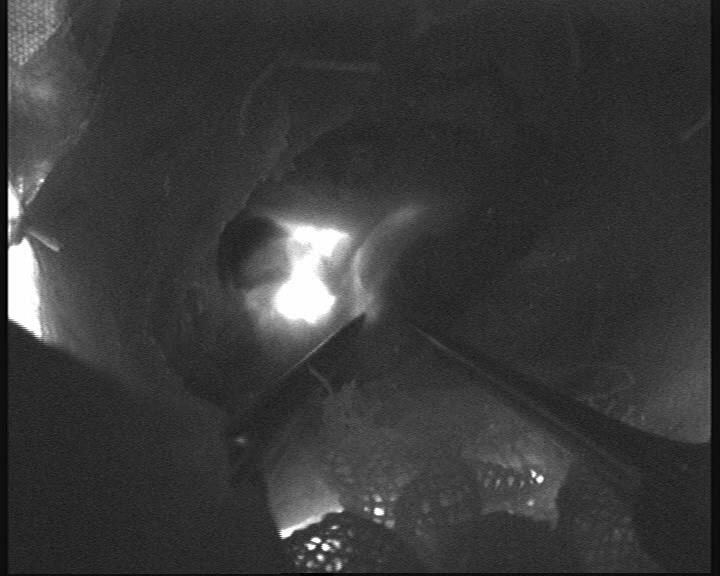

手术由神经外科缪星宇主任医师及马勃博士完成。团队在吲哚菁绿荧光显微镜引导下,通过颈部微小切口精准定位颈深淋巴结群与颈静脉,利用超显微外科技术,通过“八爪鱼”吻合方式吻合颈深淋巴-颈外静脉,建立两者间生理性引流通道,术中荧光造影引流通畅。双侧手术历时3小时余顺利完成,术中出血量不足10ml。术后患者生命体征平稳,术后2小时即恢复自主活动能力,焦虑情绪显著缓解。目前团队正密切监测其长期认知功能及影像学变化,进一步验证手术疗效。

图一 缪星宇主任医师显微镜下行颈深淋巴-颈外静脉吻合术

图二 荧光显微镜显示颈深淋巴-颈外静脉吻合良好